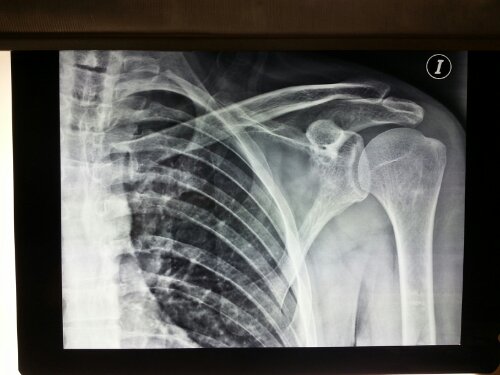

I have had bad shoulders for about 15 years now. Some days I am unable to lift my arms due to the pain. Others, they’re mostly normal. This week I have had the worse pain that I’ve had in those 15 years, so I reluctantly went to the doctor. I scheduled the appointment yesterday and had no wait when I arrived tonight. The doctor spent an hour with me, obtaining my history and conducting an examination. He then ordered xrays of both shoulders which I obtained in under 15 minutes and then he spent another 20 minutes reviewing the results, discussing next steps, and prescribing a list of medications. This has been my experience with every doctor that I’ve seen here. And the best part was that it cost me a measly 600 pesos (or roughly $48 dollars). This was the third orthopedist (and only one outside the US) I’ve seen in those 15 years and by far the best experience of all three.